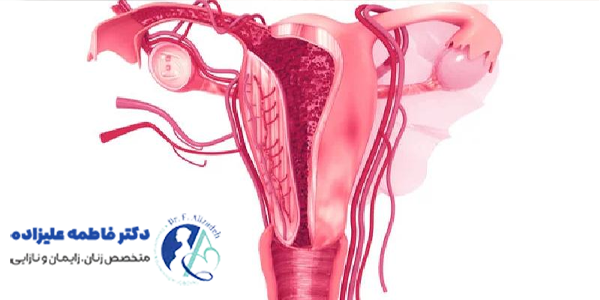

چسبندگی رحم، یکی از مشکلات شایع در دستگاه تناسلی زنان است که به اتصال غیر طبیعی بافتهای داخلی رحم به یکدیگر گفته میشود. در حالت طبیعی، پوشش داخلی رحم یا همان اندومتر، سطحی صاف و آماده برای لانه گزینی جنین است. اما در اثر آسیبهایی مثل فیبروم رحم، کورتاژهای مکرر یا عفونتهای شدید، این پوشش، آسیب دیده و بخشهایی از آن به هم میچسبند. این چسبندگیها، باعث مشکلاتی مثل اختلال در قاعدگی، درد لگنی، ناباروری یا سقطهای مکرر میشوند.

علل ایجاد چسبندگی رحم، به عواملی مربوط میشود که باعث آسیب یا التهاب در پوشش داخلی رحم اندومتر میشود. یکی از شایعترین علل، کورتاژهای مکرر به ویژه پس از سقط جنین یا زایمان است که به تخریب بافت اندومتر منجر میشود. انجام برخی جراحیهای رحمی مثل میومکتومی، هیستروسکوپی یا سزارین از دیگر دلایل مهم محسوب میشوند.

عفونتهای شدید لگنی یا رحمی، به ویژه در صورت درمان نشدن یا درمان دیر هنگام، زمینه ساز چسبندگی میشود. همچنین، گاهی برخی آسیبها به دلیل قرار دادن دستگاههای داخل رحمی یا تروماهای دیگر در رحم رخ میدهد که خطر این مشکل را افزایش میدهد. توجه به این عوامل و پیشگیری از آسیبهای غیر ضروری به رحم، در کاهش احتمال چسبندگی اهمیت مهمی دارد.